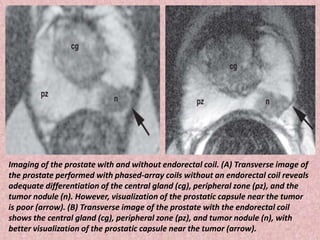

Imaging of the prostate with and without endorectal coil. (A) Transverse image of

the prostate performed with phased-array coils without an endorectal coil reveals

adequate differentiation of the central gland (cg), peripheral zone (pz), and the

tumor nodule (n). However, visualization of the prostatic capsule near the tumor

is poor (arrow). (B) Transverse image of the prostate with the endorectal coil

shows the central gland (cg), peripheral zone (pz), and tumor nodule (n), with

better visualization of the prostatic capsule near the tumor (arrow).